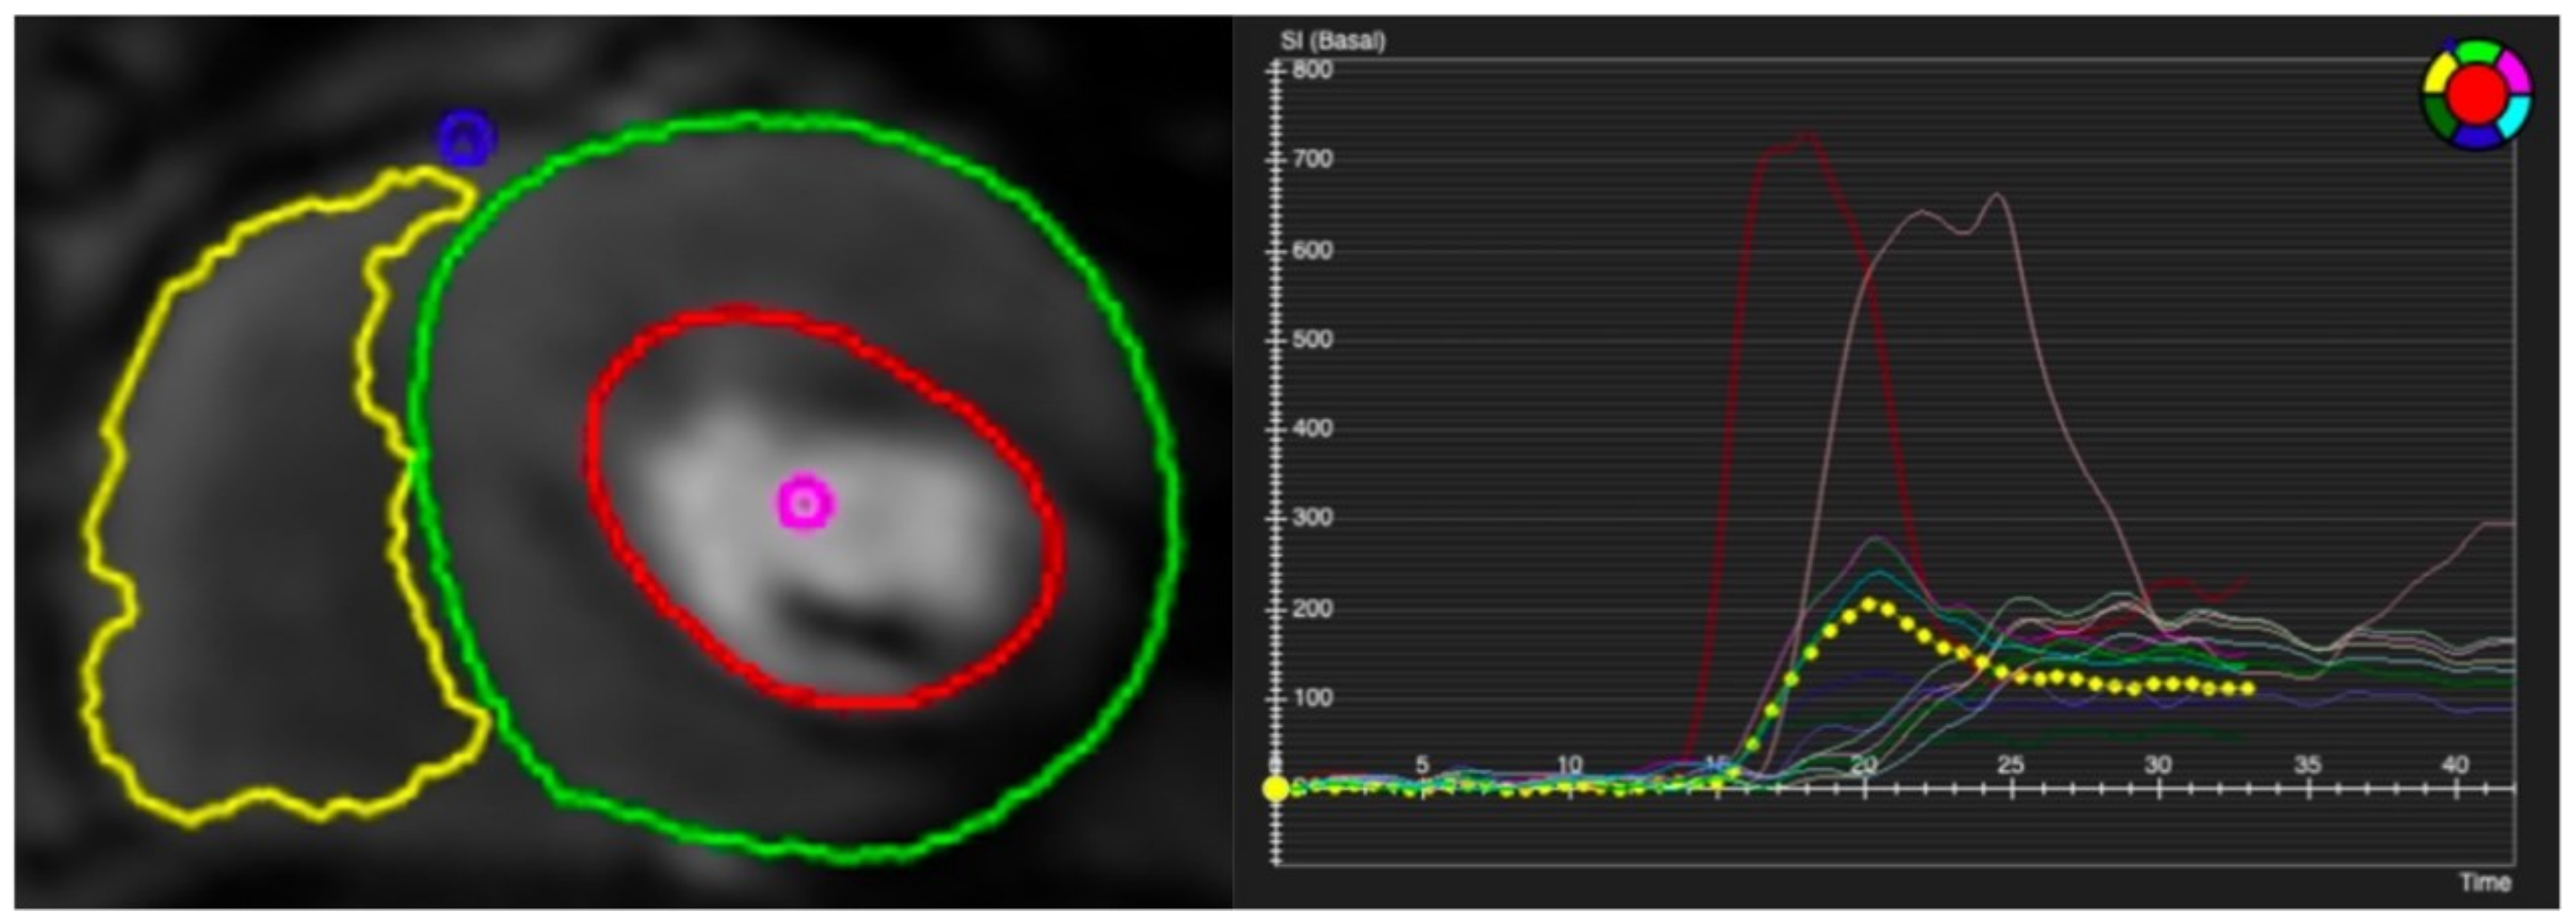

Figure 4.

Qualitative assessment of stress CMR. Subendocardial perfusion defects presented on the basal septum and mid-anteroseptal wall (red arrow) but with normal rest perfusion. Cine image shows thinner myocardium (yellow arrow) compared to remote myocardium. LGE shows subendocardial enhancement (green arrow), consistent with left anterior descending artery (LAD) infarction. As this infarct involves <50% of the wall thickness, this was regarded as viable.